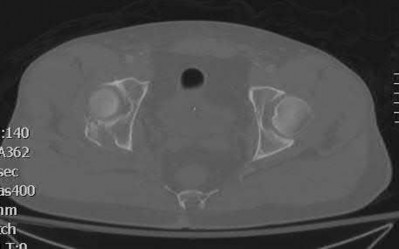

A 27 year-old patient sustains a fracture-dislocation of the acetabulum. Pelvic radiographs (Figures A and B) are taken at initial presentation and a CT scan (Figures C and D) is performed after reduction of the hip in the emergency room. What is the importance of the finding highlighted in the CT scan cuts?

The CT images shown in Figures C and D display significant marginal impaction of the joint surface.

Marginal impaction is common in posterior wall fractures and fracture-dislocations. Critical review of CT imaging of posterior wall fractures can help with preoperative planning for identifying impaction of the articular surface of the acetabulum. Restoration of the sphericity of the acetabulum to match that of the femoral head is important for successful outcome following ORIF of posterior wall fractures. A common surgical technique to accomplish joint surface restoration includes freeing the impacted articular segments, bone grafting of the void created to support the articular segments, and buttress plating of the posterior wall fracture fragments.

Patel et al. discuss the challenge of interpreting imaging of the acetabulum for assessing fracture characteristics that may significantly impact success or surgical intervention. These characteristics include: articular displacement, marginal impaction, incongruity of the joint surface, intra-articular fragments, and osteochondral injury to the femoral head. Based on expert review of images, determination of significant marginal impaction had a poor intraobserver reliability, as did each of the other modifiers listed.

Figures A and B are radiographs of the posterior wall fracture and hip dislocation. They do not show the large amount of marginal impaction of the acetabular surface. Figure C (coronal reconstruction) and Figure D (sagittal reconstruction) point out a large a amount of marginal impaction of the acetabular. Note the disruption of the joint surface on the intact portion of the acetabulum.

Incorrect answers: